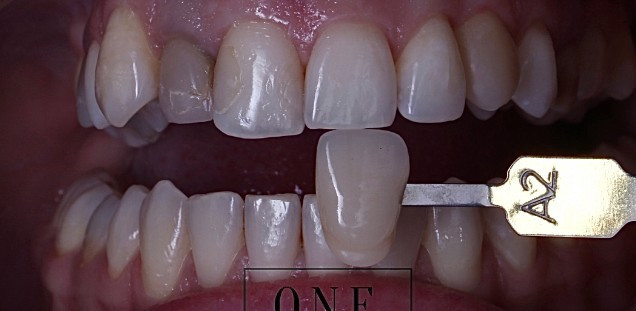

Отбеливание зубов

Внутриканальное отбеливание

Жалобы: изменение в цвете переднего зуба, после лечения в другой клинике.

Диагноз: неудовлетворительная эстетика после эндодонтического лечения, 22 зуб.

Проведена эстетическая реабилитация зуба после эндодонтического лечения, методом внутрикоронкового отбеливания препаратом Opalescence Endo.